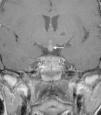

La histiocitosis de células de Langerhans (HCL) es una enfermedad rara caracterizada por la acumulación en los tejidos de células dendríticas anómalas similares a las células de Langerhans. La presentación clínica varía desde la aparición de una lesión ósea única hasta la afectación multisistémica. La implicación del sistema nervioso central (SNC), manifestada como diabetes insípida secundaria a afectación hipofisaria, es conocida desde la descripción original de la enfermedad. En la actualidad, se diferencian 2 tipos de lesiones del SNC: las lesiones seudotumorales, con infiltración por las células de Langerhans, cuya manifestación más frecuente es la infiltración hipofisaria, y otras, de más reciente descripción, las lesiones neurodegenerativas del SNC, asociadas a deterioro neurológico, que constituyen una complicación de la enfermedad de causa discutida. Nuestro objetivo es describir las manifestaciones radiológicas de la HCL en el SNC en los pacientes pediátricos.

Langerhans cell histiocytosis (LCH) is a rare disease characterized by the accumulation within tissues of anomalous dendritic cells similar to Langerhans cells. The clinical presentation varies, ranging from the appearance of a single bone lesion to multisystemic involvement. Central nervous system (CNS) involvement, manifesting as diabetes insipidus secondary to pituitary involvement, has been known since the original description of the disease. Two types of CNS lesions are currently differentiated. The first, pseudotumoral lesions with infiltration by Langerhans cells, most commonly manifests as pituitary infiltration. The second, described more recently, consists of neurodegenerative lesions of the CNS associated with neurologic deterioration. This second type of lesion constitutes a complication of the disease; however, there is no consensus about the cause of this complication. Our objective was to describe the radiologic manifestations of LCH in the CNS in pediatric patients.